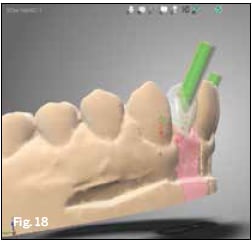

After 9 weeks of healing, minimal surgical invasion (ie, puncture incision and displacement of the tissue) in positions 7 and 10 was performed, healing screws (SC H3.5) were placed (Figure 14), and an impression was taken to produce temporary crowns for better gingiva formation and profiling (Figure 15). Following separate impression-taking (Figure 16 and Figure 17) individual restorations were designed with Straumann CARES® Visual Software 10.1 (Figure 18), produced (Figure 19), and placed.